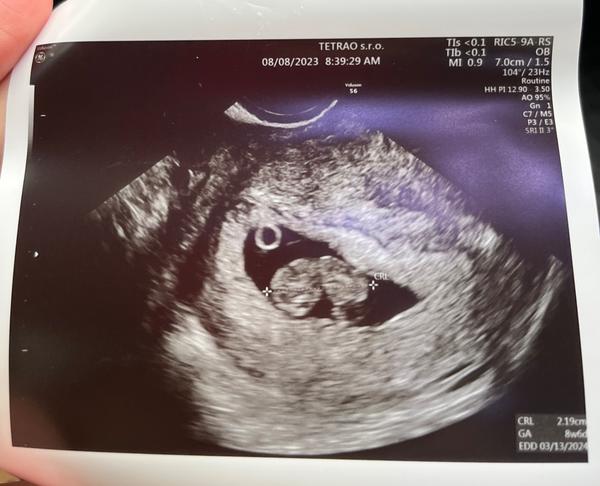

@orechova_skrupina Ahoj, ako si dnes dopadla u lekara? 🙂 U mna chvalabohu vsetko ok, ani som tomu nechcela verit, takze mi spadol kamen zo srdca a babatko zodpoveda 9 tyzdnu 🙂 ❤️😍🤗